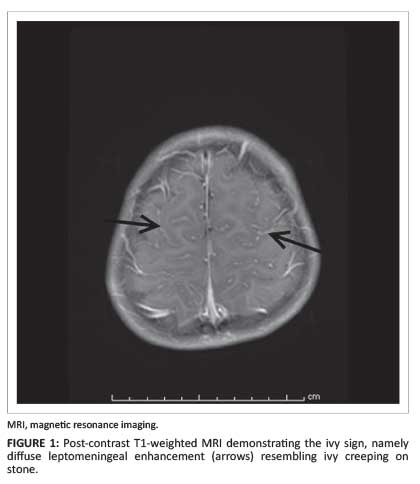

The ivy sign refers to diffuse bilateral leptomeningeal enhancement on post- contrast T1-weighted magnetic resonance imaging (MRI) and increased signal intensity in bilateral subarachnoid spaces and perivascular spaces on T2-weighted fluid attenuation inversion recovery (FLAIR) MRI sequences in patients with moyamoya disease.

Moyamoya disease is an idiopathic cerebrovascular occlusive disorder characterised by progressive stenosis of the distal aspect of the internal carotid arteries, the proximal aspects of the middle cerebral arteries and the anterior cerebral arteries, with subsequent collateral vessel formation. The ivy sign represents neovascularisation over the cerebral cortex via leptomeningeal anastomosis through collateral circulation, and represents diffuse engorgement of the pia vasculature. The ivy sign was first described in 1995, so called because of its resemblance to 'ivy creeping on stone'. The sign refers to diffuse bilateral leptomeningeal enhancement on post-contrast T1-weighted magnetic resonance imaging (MRI) (Figure 1) and increased signal intensity in bilateral subarachnoid spaces and perivascular spaces on T2-weighted fluid attenuation inversion recovery (FLAIR) MRI (Figure 2) sequences in patients with moyamoya disease.1, 2

The leptomeningeal enhancement on post-contrast T1-weighted MRI (Figure 1), seen in the ivy sign in patients with moyamoya disease, represents neovascularisation over the cerebral cortex via leptomeningeal anastomosis through collateral circulation. This develops from the anastomosis of external carotid collateral arteries and ICAs, and represents diffuse engorgement of the pia vasculature.2 This collateral flow is very slow owing to its retrograde direction via leptomeningeal anastomosis. From this phenomenon, the engorged pial network shows post-contrast enhancement.2 Recent literature suggests that 3.0-Tesla MR imaging is superior to 1.5-Tesla MR imaging in visualising the ivy sign and associated changes in moyamoya disease because of the higher resolution and increased signal-to-noise ratio and contrast-to-noise ratio, thus enabling better depiction of pathological small vessel segments, with greater angiographic detail.5